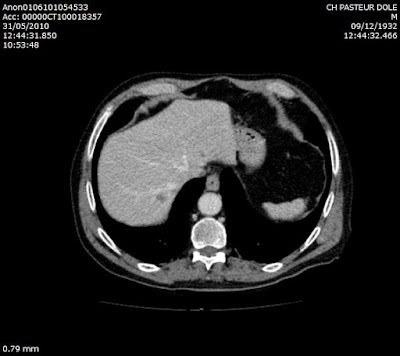

- Diffuse liver disease